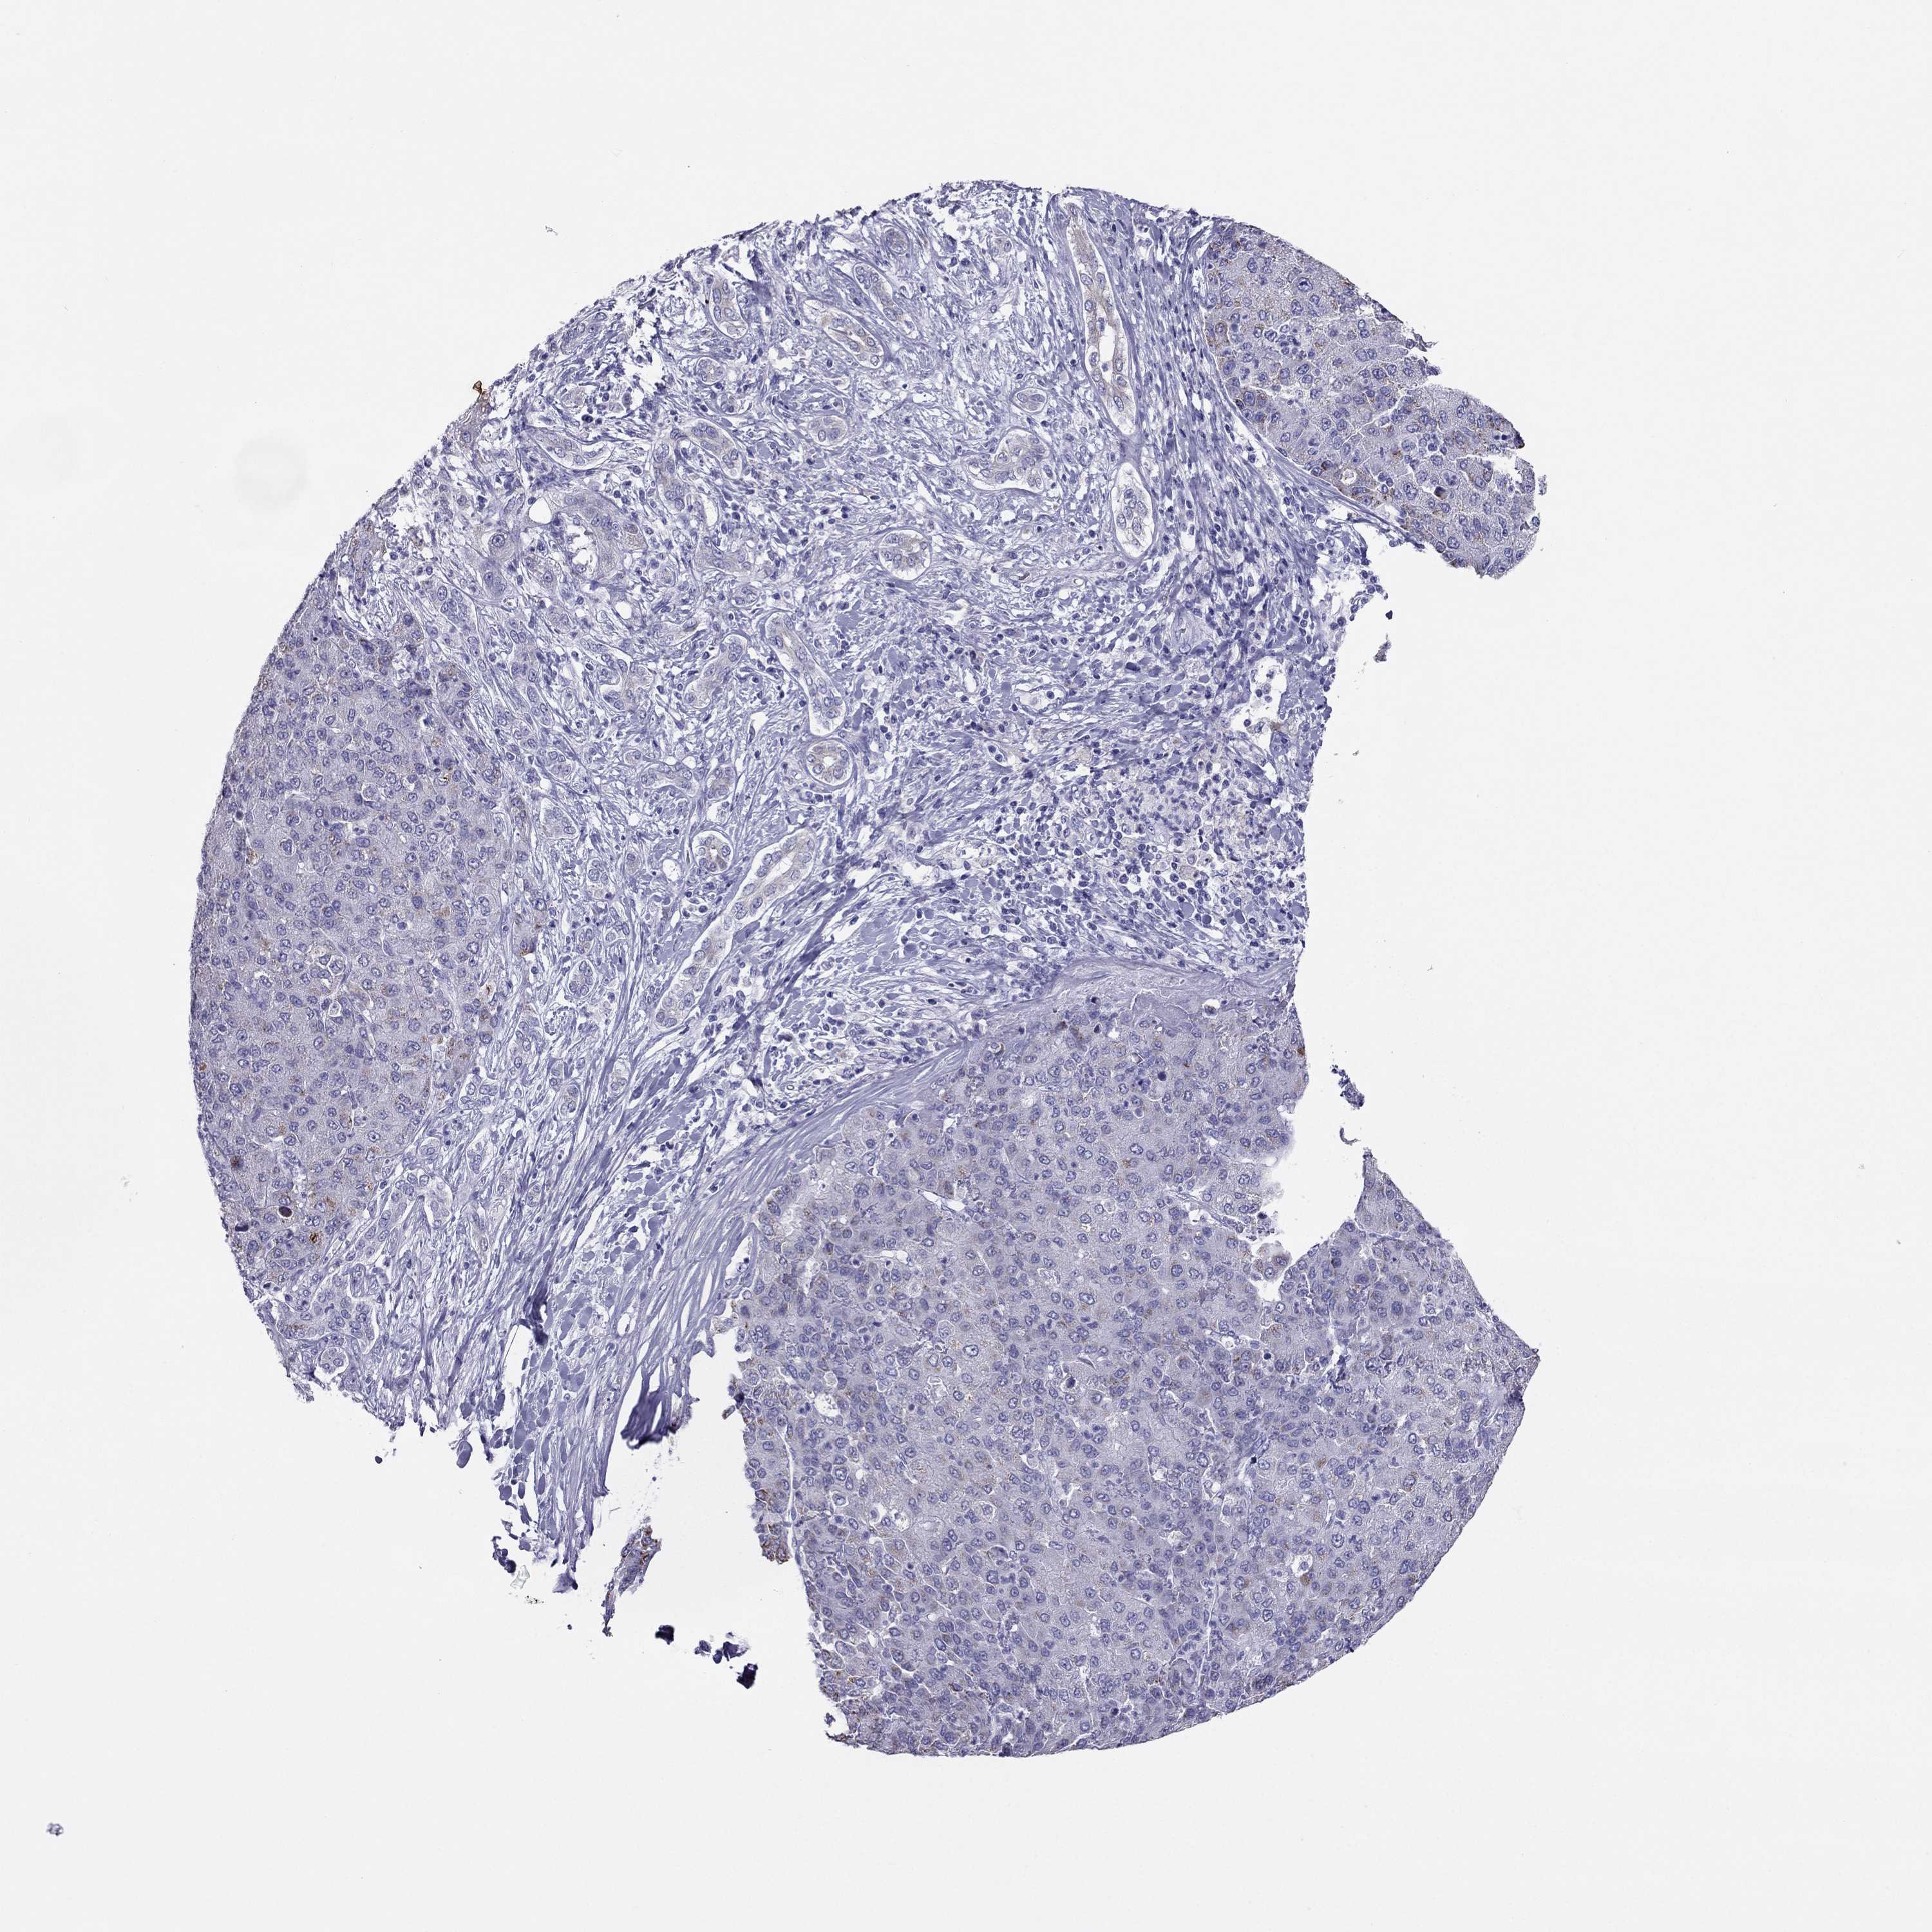

LIVER CANCER - Protein expressioni

A mouse-over function shows sample information and annotation data. Click on an image to view it in a full screen mode. Samples can be filtered based on level of antibody staining by selecting one or several of the following categories: high, medium, low and not detected. The assay and annotation is described here.

Note that samples used for immunohistochemistry by the Human Protein Atlas do not correspond to samples in the TCGA dataset.

Antibody stainingi

Antibody staining in the annotated cell types in the current human tissue is reported as not detected, low, medium, or high, based on conventional immunohistochemistry profiling in selected tissues. This score is based on the combination of the staining intensity and fraction of stained cells.

Each image is clickable and will lead to virtual microscopy that enables deeper exploration of all samples and also displays staining intensity scores, fraction scores and subcellular localization as well as patient and tissue information for each sample.

Antibody HPA078602

Staining

High

Medium

Low

Not detected

Intensity

Strong

Moderate

Weak

Negative

Quantity

>75%

75%-25%

<25%

None

Location

Nuclear

Cytoplasmic/membranous

Cytoplasmic/membranous,nuclear

Carcinoma, Hepatocellular, NOS

Cholangiocarcinoma

Adenocarcinoma, NOS